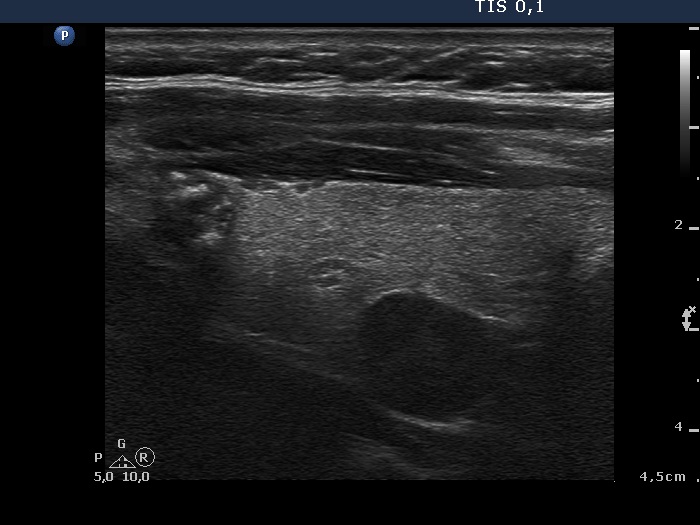

Ultrasonography: a large lesion composed of multiple moderately hypoechogenic and hyperechogenic nodules occupies almost the entire right lobe. There was a small hypoechogenic nodule in the upper pole while a cystic nodule in the central part of the left lobe. The former presented coarse and microcalcifications, too. The vascularization was not specific.

Follicular adenoma with cystic degeneration in the dorsal part of the left lobe.